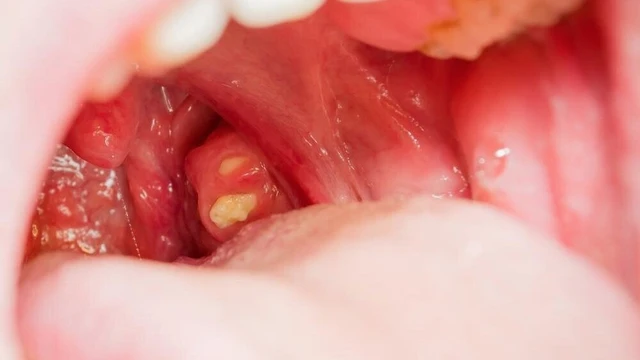

Nhiều người lo lắng khi phát hiện có hạt nằm trong ngách của amidan cùng mùi hôi khó chịu. Đây thực chất là sỏi amidan hay còn gọi là bã đậu amidan, một tình trạng phổ biến ở những người bị viêm amidan mạn tính.

Sỏi amidan là một vấn đề phổ biến nhưng thường bị bỏ qua trong cuộc sống hàng ngày bởi chúng thường ít nguy hiểm, chỉ gây ra một số khó chịu như hơi thở có mùi hoặc cảm giác vướng víu trong cổ họng. Tuy nhiên, việc loại bỏ sỏi amidan không phải là điều khó khăn. Vậy có những cách lấy sỏi amidan nào?

Tonsil stone hay còn gọi là sỏi amidan, là một vấn đề phổ biến xuất phát từ nhiều nguyên nhân khác nhau. Sỏi amidan có thể gây ra các triệu chứng như hôi miệng, đau họng và khó nuốt. Vì những lý do này, người mắc bệnh thường tìm cách loại bỏ các viên sỏi này khỏi miệng. Vậy cụ thể tonsil stone là gì? Hãy cùng Nhà thuốc Long Châu tìm hiểu qua bài viết dưới đây nhé!

Sỏi amidan là một tình trạng phổ biến do nhiều nguyên nhân khác nhau. Sỏi amidan sẽ gây ra tình trạng hôi miệng, đau họng và khó nuốt. Do đó mọi người thường tìm cách lấy những viên sỏi này ra khỏi miệng. Vậy cụ thể sỏi amidan là gì?